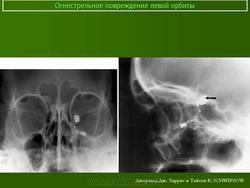

Металлическое инородное тело орбиты